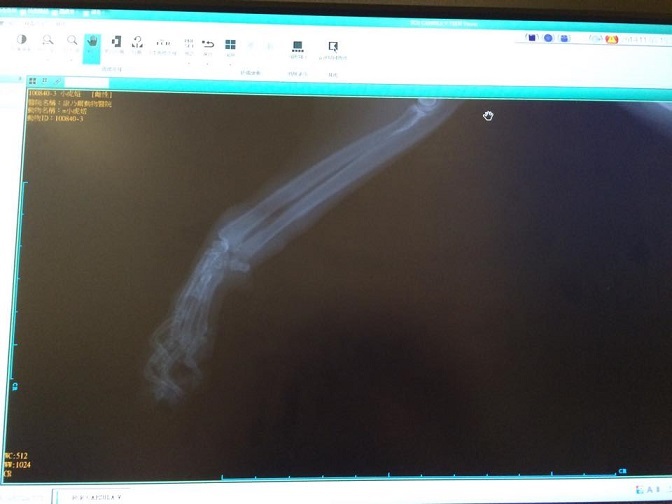

主題: 20141101前肢傷貓-虎妞 申請者姓名: 黃琦雁 花色: 申請日期: 2014-11-19 12:36:42 申請者部落格: 申請者臉書網址: 所在縣市/合作醫院: 新竹市/康乃爾動物醫院 治療費用: 2700元 需求人數: 7人 已結案 (2015-02-24 12:12:39) 報名人員: Smile Lin x2(已付款)、Smile Lin x2、林君真 x2(已付款)、貓貓(已付款)、su(已付款)、Shan Shi Lai(已付款)、 候補人員: 動物病情說明: 11/1進入竹北收容所例行性街貓出來結紮.發現一隻左前肢受傷的貓.不確定為橡皮筋貓或是捕獸夾.送醫治療

11/1起進行抗生素與傷口治療

11/3結紮與進行眼瞼修補

11/10傷口癒合非常好 已接出院

動物近況說明: 放養安全地點